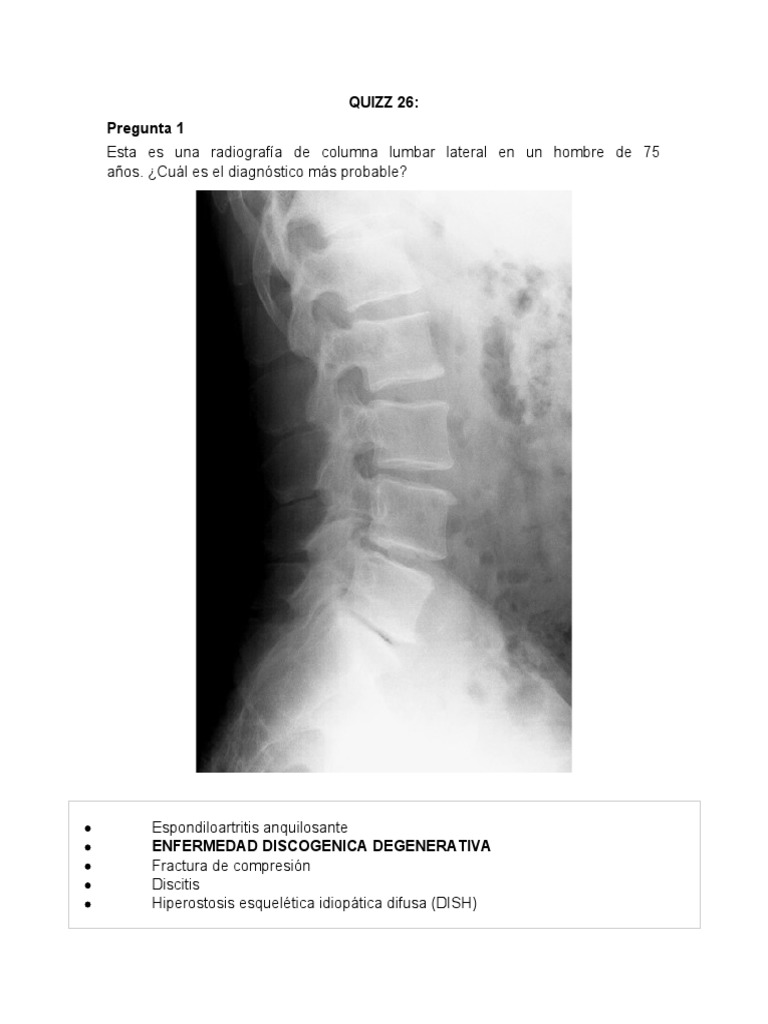

Pregunta 1

Esta es una radiografía de columna lumbar lateral en un hombre de 75

años. ¿Cuál es el diagnóstico más probable?

 Espondiloartritis anquilosante

 ENFERMEDAD DISCOGENICA DEGENERATIVA

 Fractura de compresión

 Discitis

 Hiperostosis esquelética idiopática difusa (DISH)

¡Eso es correcto!

Hay un estrechamiento del espacio del disco intervertebral en L5-S1 con

esclerosis de las placas terminales y un disco de vacío a este nivel (flecha

negra).

Con el aumento de la edad, las placas terminales de los cuerpos vertebrales

contiguos se eburnan o esclerotizan y se producen pequeños osteofitos en los

márgenes de los cuerpos vertebrales en cada espacio discal.

A veces, la desecación del disco conduce a la liberación de nitrógeno de los

tejidos que rodean el espacio discal, lo que da como resultado la aparición de

densidad de aire en el espacio discal, que se denomina fenómeno de disco de

vacío . Un disco de vacío representa un signo tardío de un disco degenerado.

Cabe señalar que los osteofitos son un hallazgo extremadamente común, que

aumenta su prevalencia con el aumento de la edad y que la mayoría de los

pacientes con osteofitos de la columna vertebral son asintomáticos.